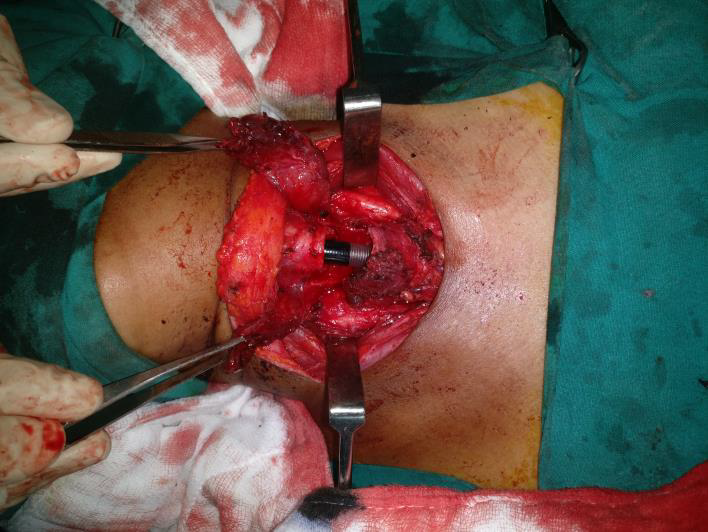

Fig 1: Trans cervical view of the trachea post resection